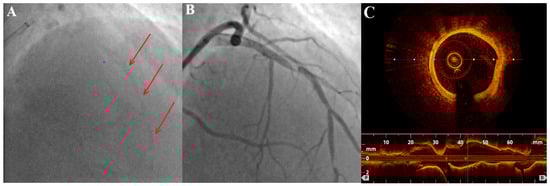

2.2. Coronary Angiography

2.3. Intravascular Imaging: IVUS (Intravascular Ultrasound) and OCT (Optical Coherence Tomography)